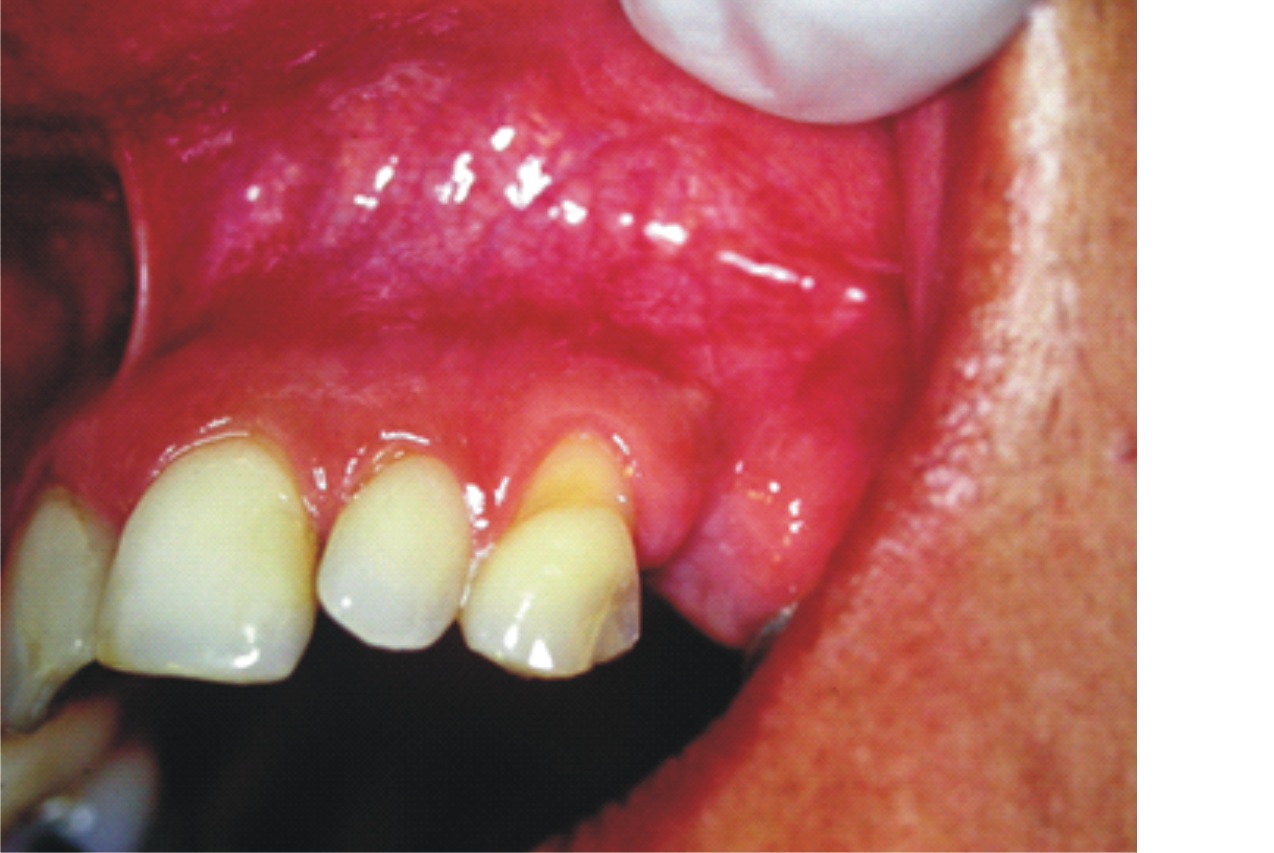

- Figura 2 (Português (Brasil))